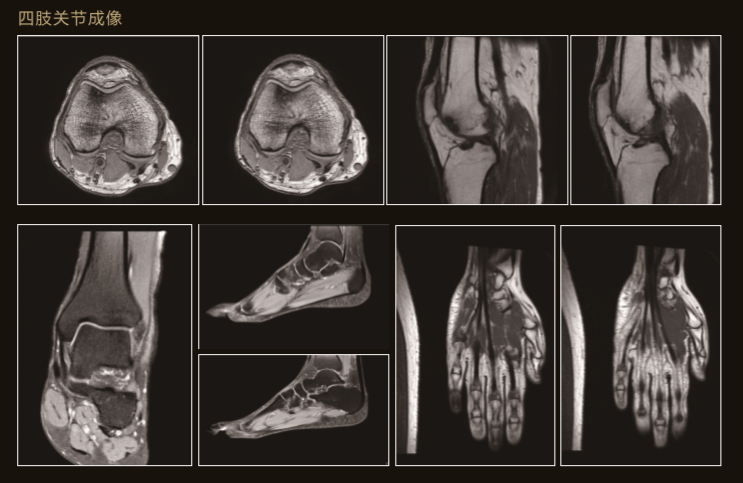

臨 床 圖 集

Apsaras飛天保持高操作性能的同時進一步追求臨床價值

Apsaras飛天不僅采用極高均勻度的磁體系統,還配備了高階勻場系統可大範圍的高階磁場校正,以獲得具有臨床價值的圖像。

Apsaras飛天在保持以往使用便捷的前提下,應用程序支持更全面的臨床應用和發展。